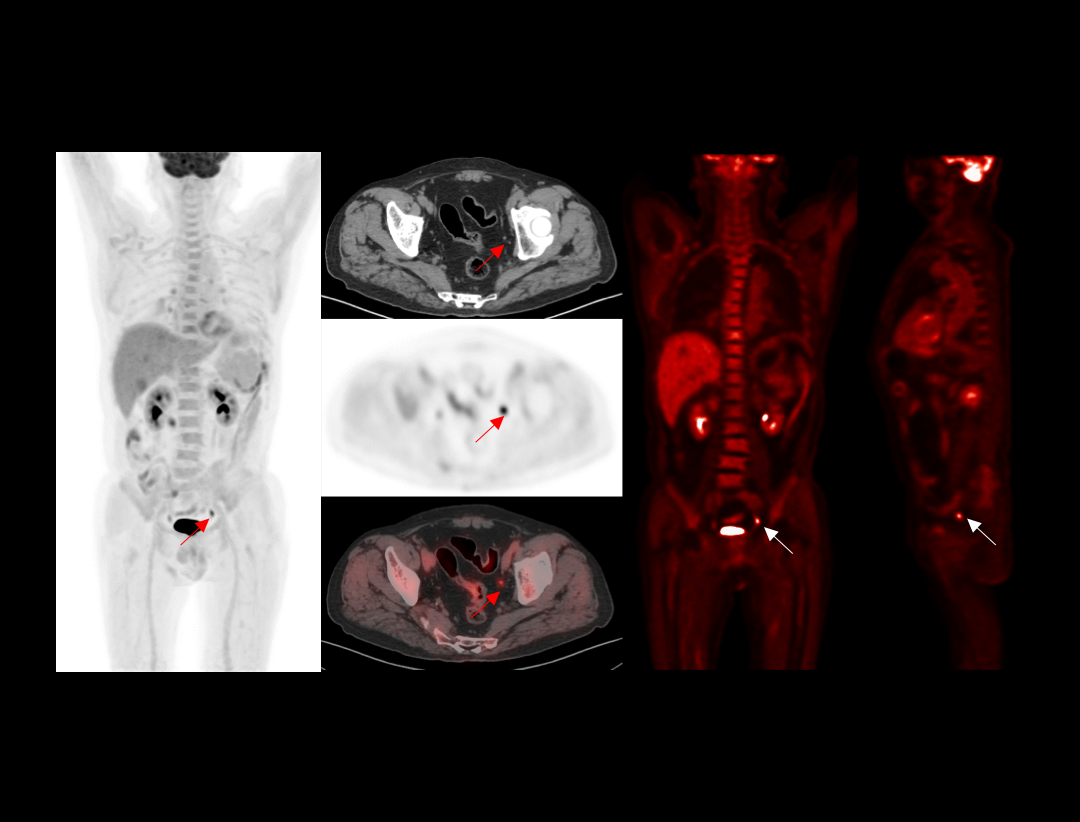

全真数字PET与160层北斗CT强强联手,将高品质的功能影像与解剖学影像精准融合,显著提升微小病灶检测精度,全面助力肿瘤、心脏和神经等重大疾病领域的精准诊疗。

2.9mm NEMA分辨率

硬件源头提升空间分辨率近40%*

*相较于空间分辨率为4mm的PET-CT系统

HYPER Iterative®4D全迭代算法

软件算法保障PET图像高清还原